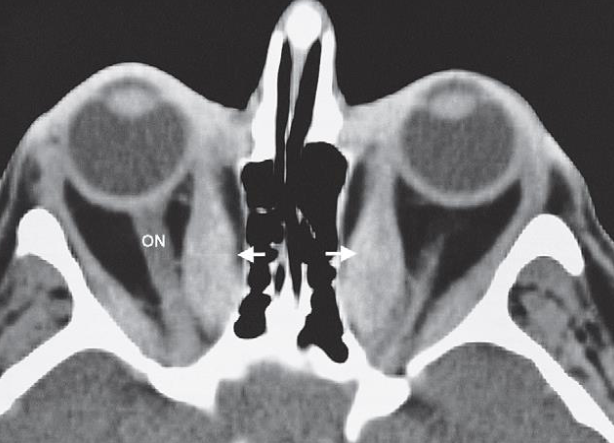

- Thyroid eye disease.

- CT scan through the orbits

- showing enlargement of the extraocular muscles, particularly the medial rectus (arrows).